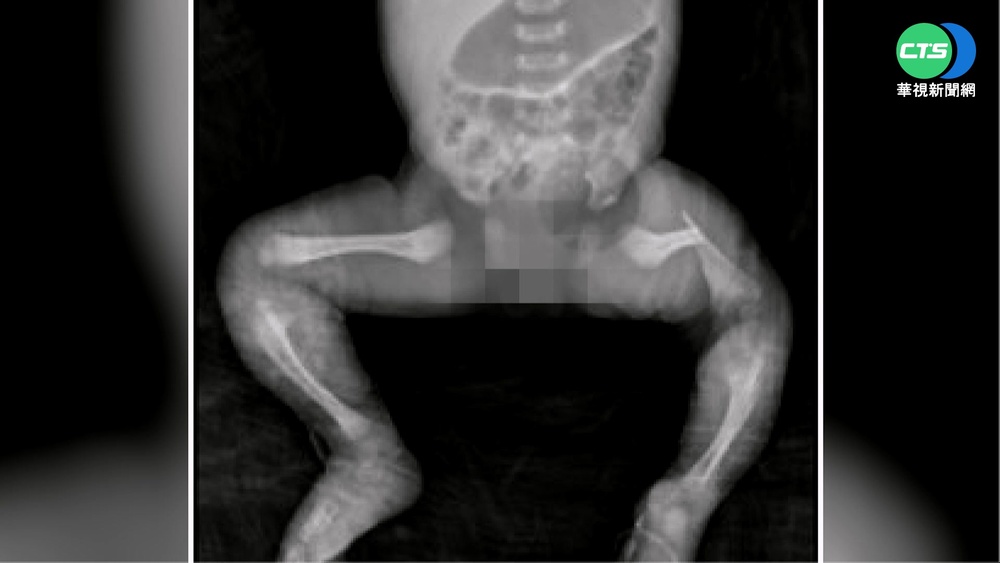

才剛出生的小男嬰,細嫩的屁屁上,出現大片紅腫傷口,只要碰觸就痛到大哭,看在媽媽眼裡實在好心疼,她說帶著兒子,入住台南一間月子中心,一開始屁股紅疹只有幾顆,卻沒想到第3天後,紅屁屁越來越嚴重,當事媽媽說:「換了奶粉但是屁屁一直都沒有好,擦了藥膏都沒有好。」孩子沒有食慾,體重天天下降,想帶孩子出去看醫生,被護理師告知說不用,因為妳帶去哪小孩都是一樣的,但兒子皮膚越來越糟,媽媽擔心得不得了,堅持帶他去其他醫院檢查,才發現尿布沒勤換。

當事媽媽說:「他(醫生)說就是沒有很勤的換尿布,護理師那種態度我覺得滿差勁的。」家屬痛心認為,是月子中心照顧不周,而月中則強調,沒有照護疏失,當事機構人員說:「小朋友一入住的時候,他的屁股皮膚狀況就已經是受損的,疑慮都是照著兒科醫師巡診,兒科醫囑下去做照護,他也是叫我們晾屁股藥膏使用。」